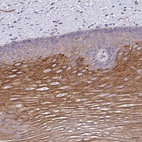

Immunohistochemical staining of human esophagus shows strong cytoplasmic positivity in squamous epithelial cells.